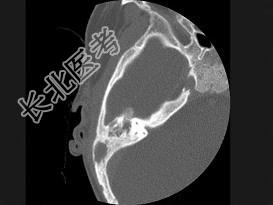

- 单项选择题女性,17岁, 右耳乳突区隐痛,右耳后乳突区出现包块, 逐渐增大,CT检查如图所示, 请选择最可能的 ( )